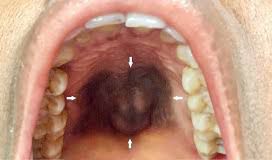

Melanoacanthoma is a rare cutaneous tumor reported more commonly in light skinned persons. The lesions are usually solitary and common sites are the head, neck, trunk, often on the lip or the eyelid. Some have suggested that it could be a localized phenomenon induced by trauma.